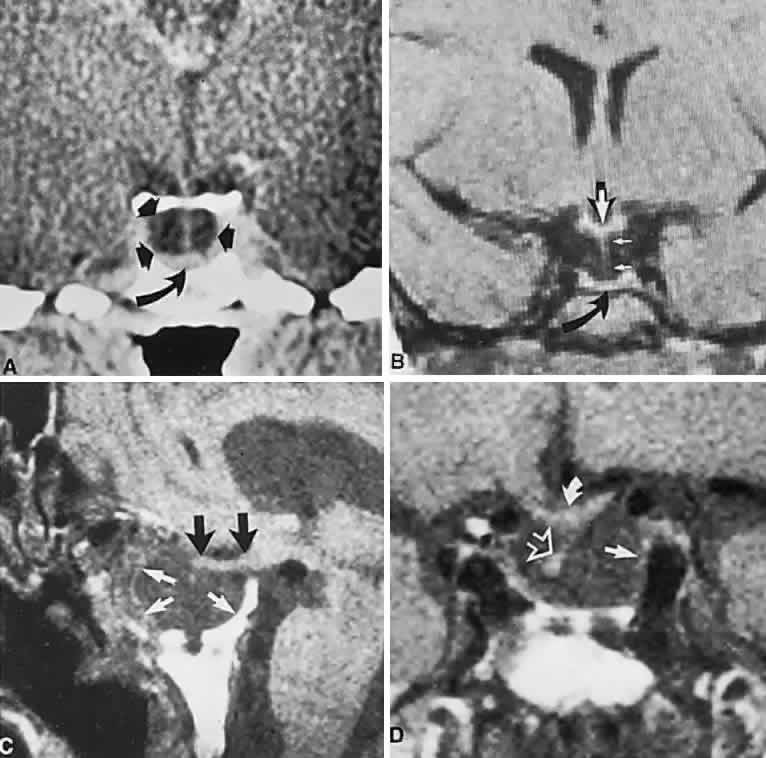

The absence of field defects, for example, in patients undergoing evaluation for amenorrhea, galactorrhea, or sellar enlargement incidentally discovered, does not imply the absence of an adenoma. Obviously, patients with microadenomas, that is, confined within the sella, do not have field defects. From a study24 of 50 cases of pituitary adenomas with chiasmal syndrome, it was concluded that visual disturbance occurs when the chiasm is displaced approximately 10 mm upward (see also Volume 2, Chapter 4, Fig. 6). The modern management of pituitary adenomas should involve several disciplines: current neuroradiologic studies detect microadenomas and provide precise delineation of gross morphology and status of neighboring structures, and mixed MRI signals suggest new or old hemorrhage, cysts, and so forth (Fig. 2); radioimmunoassay techniques assay PRL and other endocrine levels; oral neuropharmacologic agents, such as bromergocryptine, provide a “medical adenomectomy” for hyperprolactinemia and acromegaly; transsphenoidal surgery, including high-illumination microscopical procedures, televised radiofluoroscopic monitoring, and infection control, has all but replaced transcranial approaches; immunohistochemistry techniques have replaced the anachronistic tinctorial designations (e.g., chromophobe, basophilic) with a functional classification.

Fig. 2. Large prolactinoma. Original vision in the right eye (RE) was 8/200, left eye (LE) 1/200, with serum prolactin of 26,000 ng/ml and galactorrhea. Four months of bromocriptine reduced prolactin to 661 ng/ml, vision improved to RE 20/40, LE 20/50. At 3 years, vision was as follows: RE 20/30, LE 20/20; prolactin was 25.9 ng/ml. Enhanced magnetic resonance imaging. Sagittal (A) and coronal (C) images at diagnosis. Sagittal (B) and coronal (D) images at 2-year follow-up, showing dramatic shrinkage of the mass.

Imaging of Pituitary Tumors

In addition to the radiologic implications mentioned previously, specific points should be emphasized. Contrast-enhanced CT and, especially, MRI have replaced all previous radiologic techniques in the detection and anatomic assessment of sellar and juxtasellar lesions. MRI has also the inherent advantage of using no radiation, nor does it require iodinated contrast injections. Although thin-section contrasted CT does indeed disclose most lesions, bone changes, and recent hemorrhage, MRI is superior in delineating distortions of optic nerves and chiasm, in displaying arteries, and in revealing fat, hemorrhage, or cyst (see Figs. 3E through M). Indeed, in a prospective study of normal volunteers, gadolinium-enhanced MRI disclosed pituitary adenomas (3 mm to 6 mm in diameter, i.e., microadenomas) in 10% of adults aged 18 to 60 years.66 T2-weighted fast spin-echo MRIs are currently the most precise sequence for demonstrating the optic nerves and chiasm, even when these structures are severely distorted by suprasellar tumor extension.67